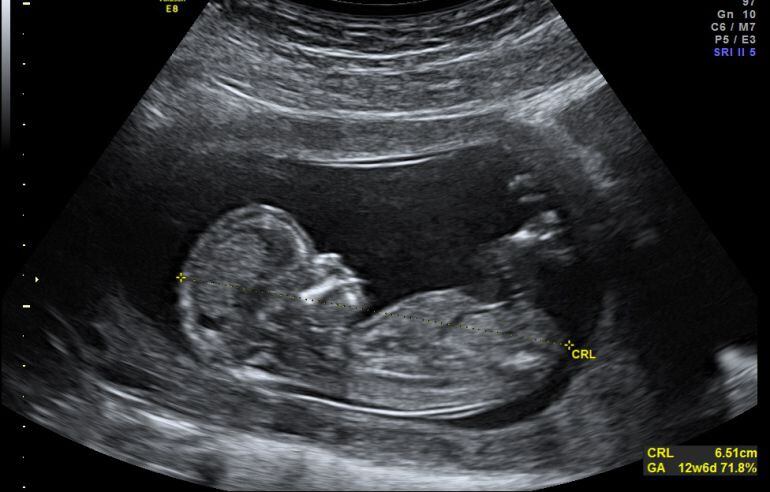

Ecografía de un bebé / Cadena SER

En total, según consta en los informes, se realizaron cinco ecografías calificadas todas ellas como "normales" y sin detección de anomalía alguna o hallazgo patológico, ni la concurrencia de circunstancias particulares de la embarazada que pudieran dificultar la visión del feto.

En concreto, en la ecografía 20 se apreciaba "complitud" de las extremidades superiores e inferiores del feto, sin anomalía o malformación algunas, lo cual, aún tratándose de una técnica no infalible y de limitada capacidad diagnóstica pese a su alta detectabilidad pero con variable sensibilidad, "pone de manifiesto el error de diagnóstico en que se incurrió reiterado en todas las ecografías".